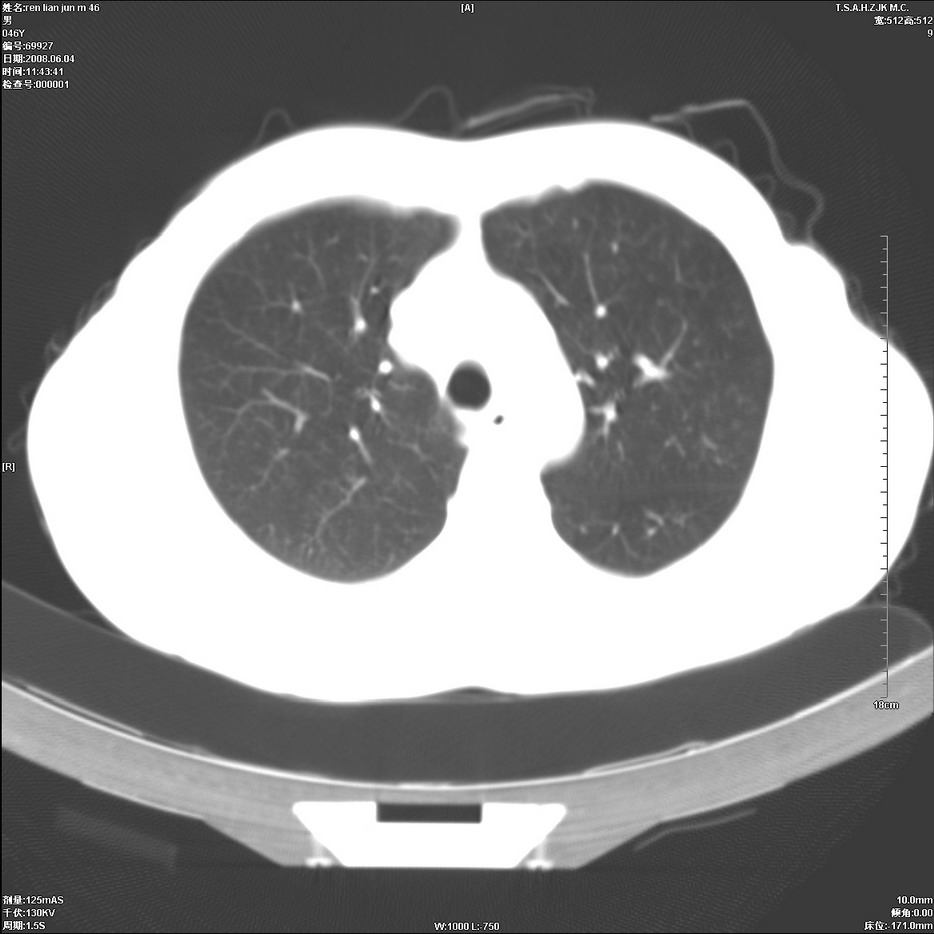

以下是引用qiu999在2008-6-5 17:14:00的发言:[br]考虑右肺中心型肺癌.颅内应做增强检查.

以下是引用形影不离在2008-6-5 19:18:00的发言:[br]右肺中心型肺癌并纵隔及左侧腋窝淋巴结转移,颅内应做增强检查。

以下是引用杀毒软件在2008-6-5 18:33:00的发言:[br]支持考虑右肺中心型肺癌,颅内病变是不是转移,不好说